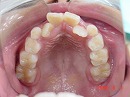

今回の場合、歯並びが悪い原因は 上顎が小さい事 でした。

拡大 矯正前 矯正後

診査・診断の結果、

上顎の大きさを約10ミリ大きくしなくてはならないことがわかりました。

今回の症例は、約6カ月ほどで改善しています。

しかし、拡大だけで将来の歯並びが良くなる訳ではありません。

矯正は、奥が深いのです…。